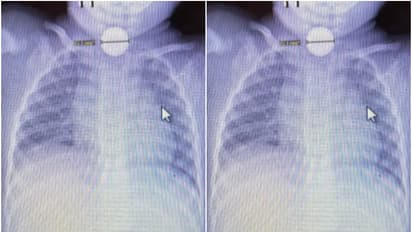

അമേരിക്കയിലെ ടെക്സസിലാണ് സംഭവം. കടുത്ത വയറുവേദനയെ തുടര്ന്ന് കുഞ്ഞ് നിലവിളിച്ചതോടെയാണ് അമ്മയായ മഡലൈന് ഡൺ കുഞ്ഞിനെ ഉടൻ തന്നെ ആശുപത്രിയിലെത്തിച്ചത്. രാത്രി 11 മണിയോടെയാണ് കൈ എന്ന കുഞ്ഞ് ഉണര്ന്ന് നിലവിളിച്ചത്. അസഹനീയമായ വേദന കൊണ്ട് പുളഞ്ഞ കുഞ്ഞിനെ ആശുപത്രിയിലെത്തിച്ചപ്പോള് ആദ്യം വയറ്റില് വൈറസ് ബാധയാണെന്നാണ് ഡോക്ടര്മാര് കരുതിയത്. കുഞ്ഞ് എന്തോ വിഴുങ്ങിയെന്ന സംശയം ഉള്ളതിനാല് അമ്മയുടെ അഭ്യര്ത്ഥന പ്രകാരം ഡോക്ടര്മാര് എക്സ്റേ എടുത്തു. ഇതോടെയാണ് ബട്ടൺ ബാറ്ററി കുഞ്ഞ് വിഴുങ്ങിയതായി കണ്ടെത്തിയത്. പെട്ടെന്ന് തന്നെ ഡോക്ടര്മാര് അടിയന്തര ശസ്ത്രക്രിയ നിര്ദ്ദേശിക്കുകയായിരുന്നു. കുഞ്ഞിനെ അടിയന്തര ശസ്ത്രക്രിയക്ക് വിധേയനാക്കുകയുമായിരുന്നു.